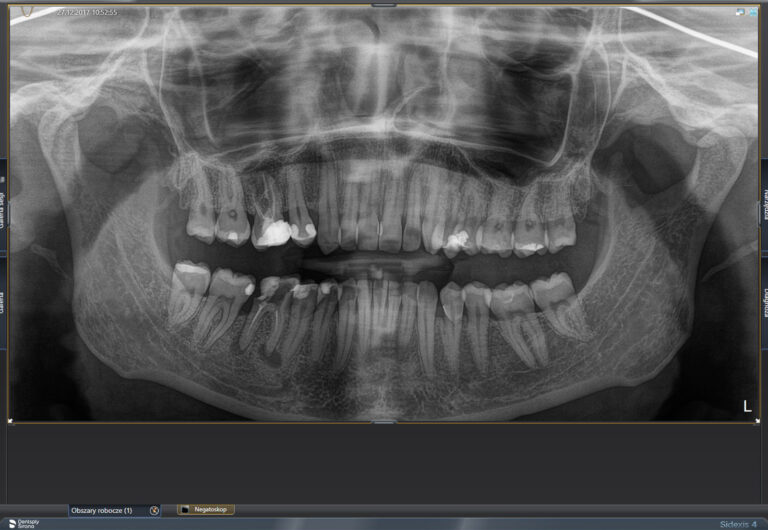

W naszych gabinetach oferujemy wykonanie wielu rodzajów zdjęć rtg. Są to nieinwazyjne badania obrazowe uzupełniające diagnostykę, w związku z czym na pierwszej wizycie zwykle wykonywane jest zdjęcie panoramiczne zębów. Pozwala ono ocenić stan wszystkich zębów i tkanek okolicznych.

Zdjęcia ortopantomograficzne ( nazywane panoramicznymi),